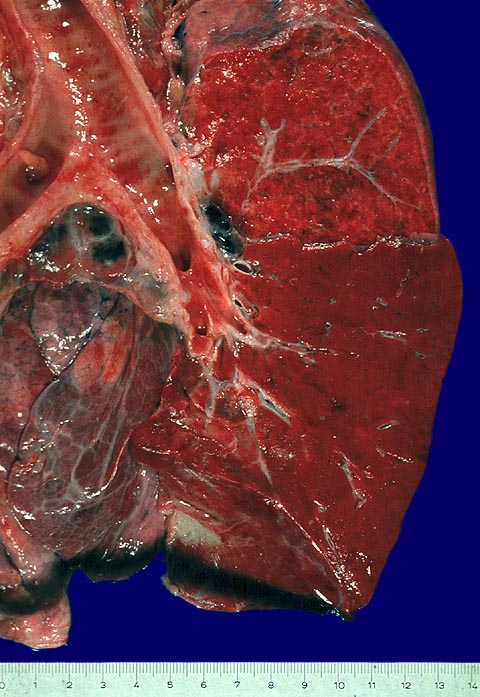

Lobärpneumonie: rote Hepatisation

Die Schnittfläche des Lungenunterlappens erscheint homogen rot, stark verfestigt und erinnert dadurch an Leberparenchym. Der Oberlappen ist nicht betroffen.

Mikroskopisch besteht eine Fibrinausfällung in den Alveolen und die Kapillaren sind prall mit Blut gefüllt.

2. bis 3. Tag einer Pneumokokkenpneumonie.